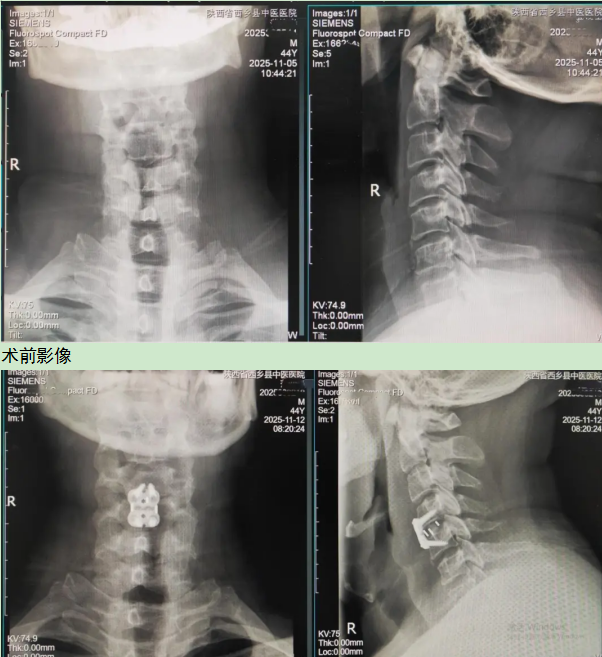

患者因长期被颈部疼痛、右上肢剧烈放射性麻木和疼痛所困扰,并出现握力明显下降,日常生活受到严重影响。经主管医生许向前详细检查并结合颈椎MRI,最终诊断为:脊髓型颈椎病、颈椎间盘突出症、颈椎椎管狭窄并伴有颈椎骨质增生。影像结果显示,其突出的椎间盘组织已严重压迫脊髓与神经根,病情危急,如不及时手术,神经功能将持续受损,甚至面临高位截瘫的风险。

“手术仅通过一个3-4厘米的微小切口,我们便能精准抵达病变椎间隙。”魏主任解释道,“在显微镜或放大镜的辅助下,我们彻底清除了压迫脊髓和神经根的‘罪魁祸首’–突出的髓核组织,为神经进行了完美‘松绑’。随后,为重建颈椎的稳定与高度,我们植入了量身选择的椎间融合器,并采用钛合金钢板进行内固定。”整台手术如行云流水,出血量极少,神经结构保护完好,从根本上为患者解除了病痛。